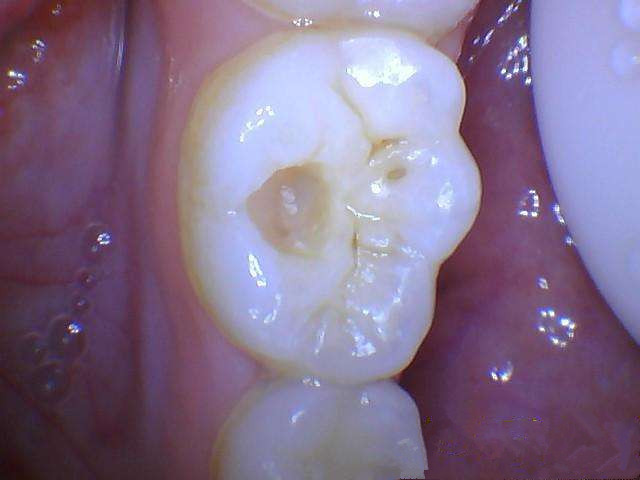

第1阶段:牙齿咬合面有黑线,一般见于大牙,说明开始蛀牙了,牙釉质遭腐蚀,但不痛不痒,一般很难发现。这时候应及时补牙,而不是洗牙。费用大概在300左右。

第2阶段:牙齿上明显龋洞,细菌腐蚀到牙本质,对冷热酸甜敏感,这时候需要是腐质去除进行补牙即可。